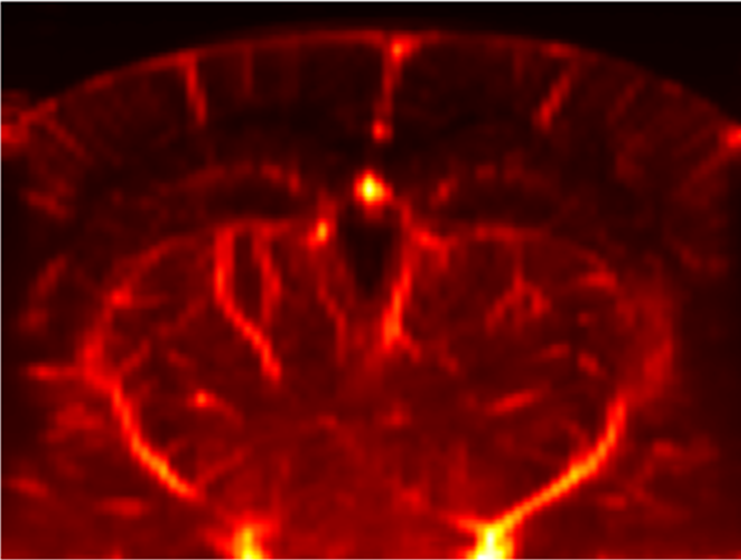

Example of artefact we will try to correct in this step

Example motion in a awake, head-fixed mouse while the animal moves. Deformations are more visible in deep parts of the brain.

This brain motion is present when animals move and more likely in bigger, stronger animals.